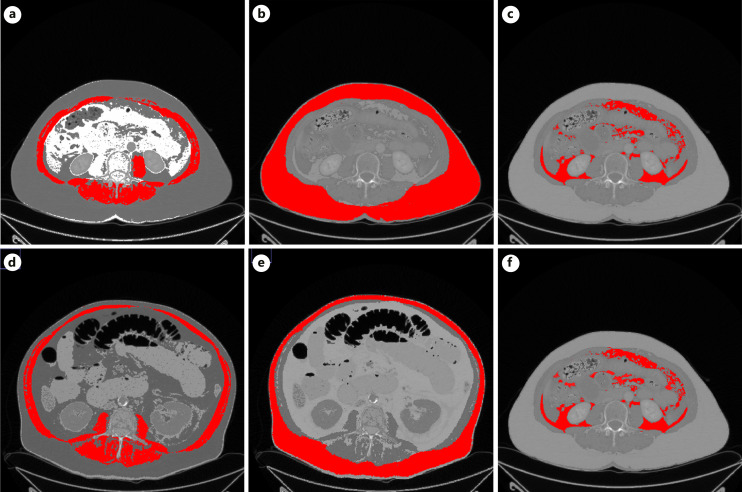

Introduction: Body composition comprising low-skeletal muscle mass (LSMM) and subcutaneous and visceral adipose tissue (SAT and VAT) can be assessed by using cross-sectional imaging modalities. Previous analyses suggest that these parameters harbor prognostic relevance in various diseases. Aim of this study was to analyze possible associations of body composition parameters on mortality in patients with clinically suspected acute mesenteric ischemia (AMI).

Methods: All patients with clinically suspected AMI were retrospectively assessed between 2016 and 2020. Overall, 137 patients (52 female patients, 37.9%) with a median age of 71 years were included in the present analysis. For all patients, the preoperative abdominal computed tomography (CT) was used to calculate LSMM, VAT, and SAT.

Results: Overall, 94 patients (68.6%) of the patient cohort died within 30 days within a median of 2 days, range 1-39 days. Of these, 27 patients (19.7%) died within 24 h. According to the CT, 101 patients (73.7%) were classified as being visceral obese, 102 patients (74.5%) as being sarcopenic, and 69 patients (50.4%) as being sarcopenic obese. Skeletal muscle index (SMI) was lower in non-survivors compared to survivors (37.5 ± 12.4 cm2/m2 vs. 44.1 ± 13.9 cm2/m2, p = 0.01). There were no associations between body composition parameters with mortality in days (SMI r = 0.07, p = 0.48, SAT r = -0.03, p = 0.77, and VAT r = 0.04, p = 0.68, respectively). In Cox regression analysis, a nonsignificant trend for visceral obesity was observed (HR: 0.62, 95% CI: 0.36-1.05, p = 0.07).

Conclusion: SMI might be a valuable CT-based parameter, which could help discriminate between survivors and non-survivors. Further studies are needed to elucidate the associations between body composition and survival in patients with AMI.